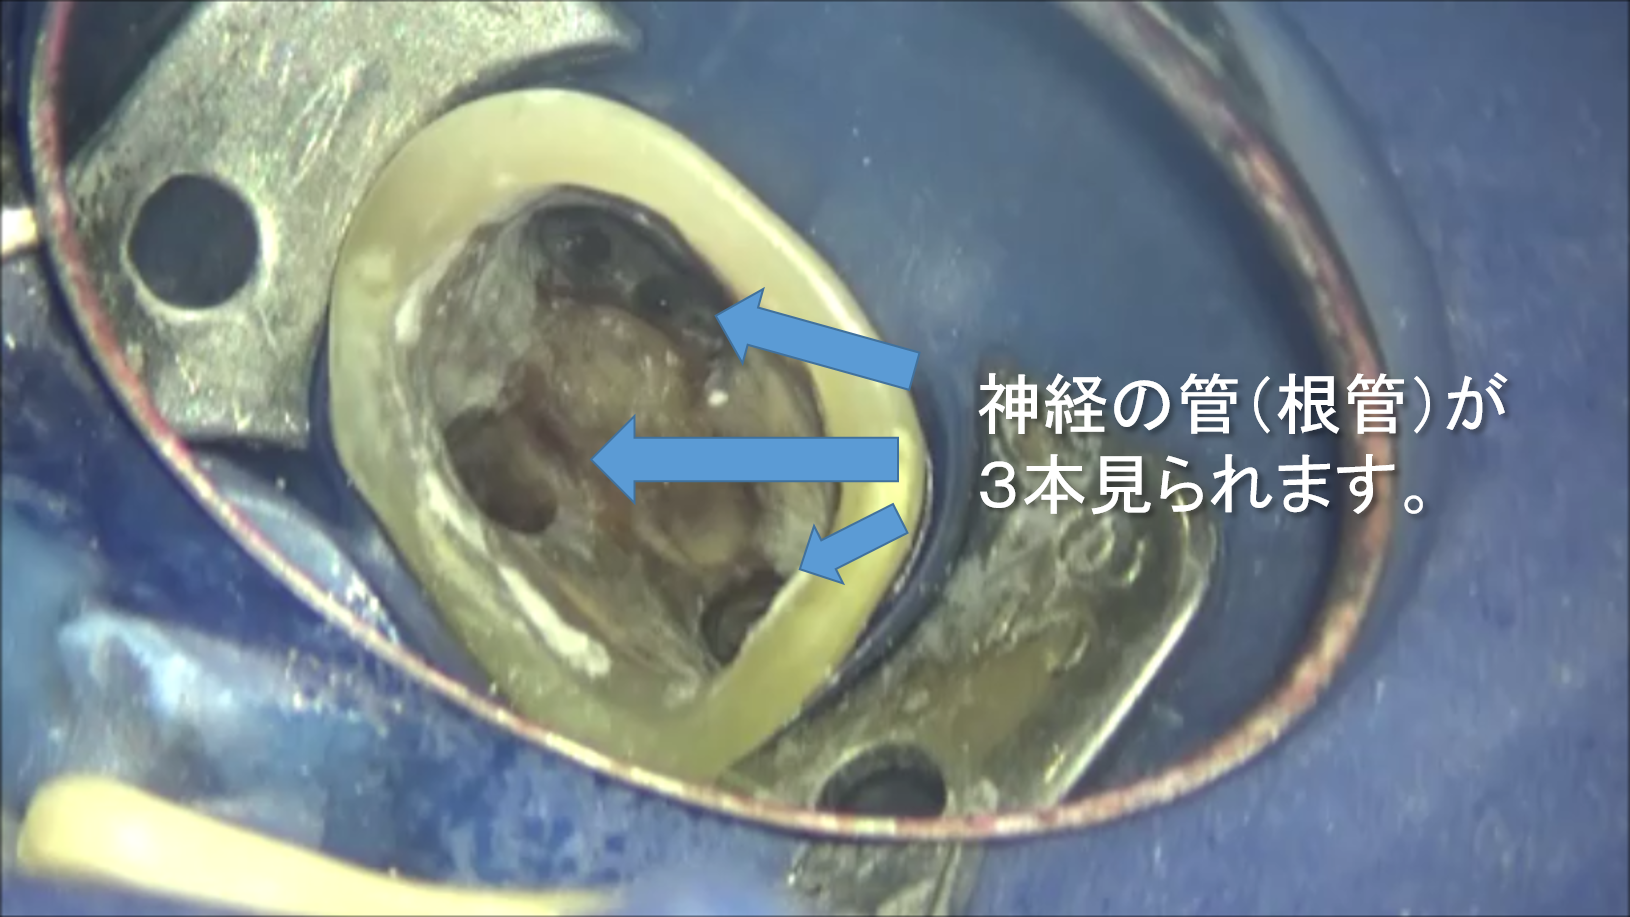

専門根管治療 根管内の清掃編

こんにちは。 南館歯科クリニックの木村です。 当院で行っている専門根管治療(マイクロエンド)の症例をご紹介します。 このケースは、金属の被せ物で治療がしてあった歯です。 ときどき違和感がある程度で、自…